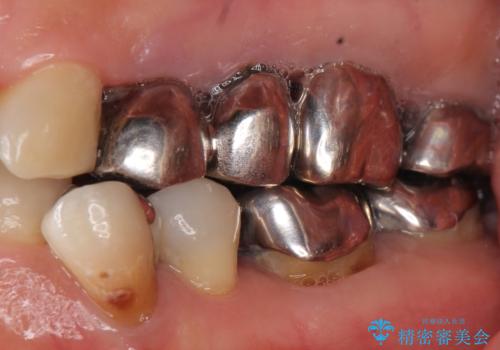

セラミッククラウンの自然な仕上がりと咬み心地に大変ご満足頂けました。

歯がしみる症状もなくなり、外側に出ていた歯が気にならなくなったと喜んで下さいました。

クラウンの種類:オールセラミッククラウン エコノミー